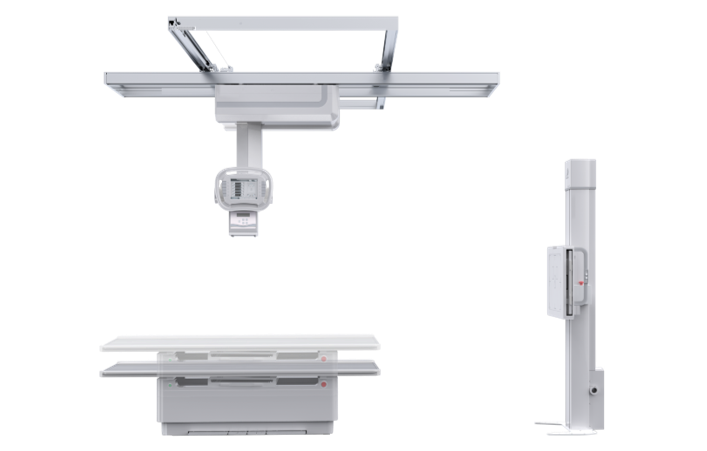

PLD7600

多功能懸吊動態DR

一機多用 PLD7600

一機多用 PLD7600

● 智能升降床體

智能升降床設計,便于老、幼、病殘或行動不便者上下床,給患者以及醫護人員帶來更舒適的檢查體驗,智能化程度極高。

● 雙向自動跟蹤

探測器與球管雙向自動跟蹤,無需手動校正,多角度高精度實時同步;

胸片位、床上位電動轉換,一鍵到位。

● 低位攝影

球管及胸片架可大范圍縱向移動,平板探測器中心最低離地35cm,輕松滿足膝關節、踝關節等低位攝影的要求。

● 特殊角度攝影

牛頭可全角度旋轉,滿足全身各部位的應用,特有的傾斜投照位,可滿足特殊病人的臨床應用。

● 手動電動一體化

懸吊配備手動模式與電動模式,沿天軌橫縱移動時可選手動或電動,滿足不同醫護人員使用習慣。

● 自動對中

球管自動對準探測器中心點,無需手動校準,便捷高效。

● 自動控制曝光

無需手動調節,系統準確地控制射線劑量,獲得適當的感光量,保證優秀的影像效果。

● 圖像拼接

系統可以識別曝光圖像,無需設置識別點即完成精準拼接,呈現大范圍完整影像。

● 平板在線充電技術

胸片架或攝影床的片盒系統內置在線充電口,快速充電,持久續航。